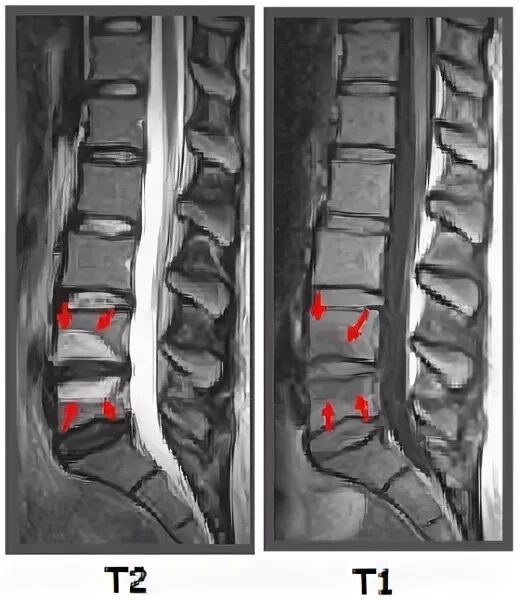

Грыжа шморля позвоночника симптомы и лечение